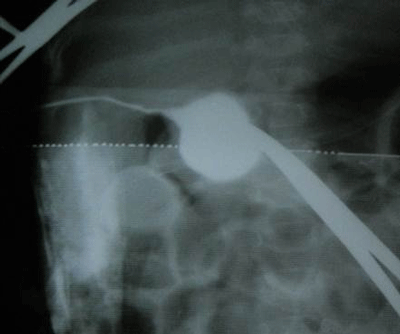

Needle aspiration did not reveal any bile. The above findings were confirmed by intra-operative cholangiography which demonstrated the cystic duct opening into a cystic structure similar to a CDC. The intra-hepatic ducts were not visualized and there was no dye in the duodenum (Fig. 2).

Figure 2: Peroperative cholangiogram showing gall bladder draining into CDC with lack of opacification of proximal hepatic ducts and no dye seen entering the duodenum. |